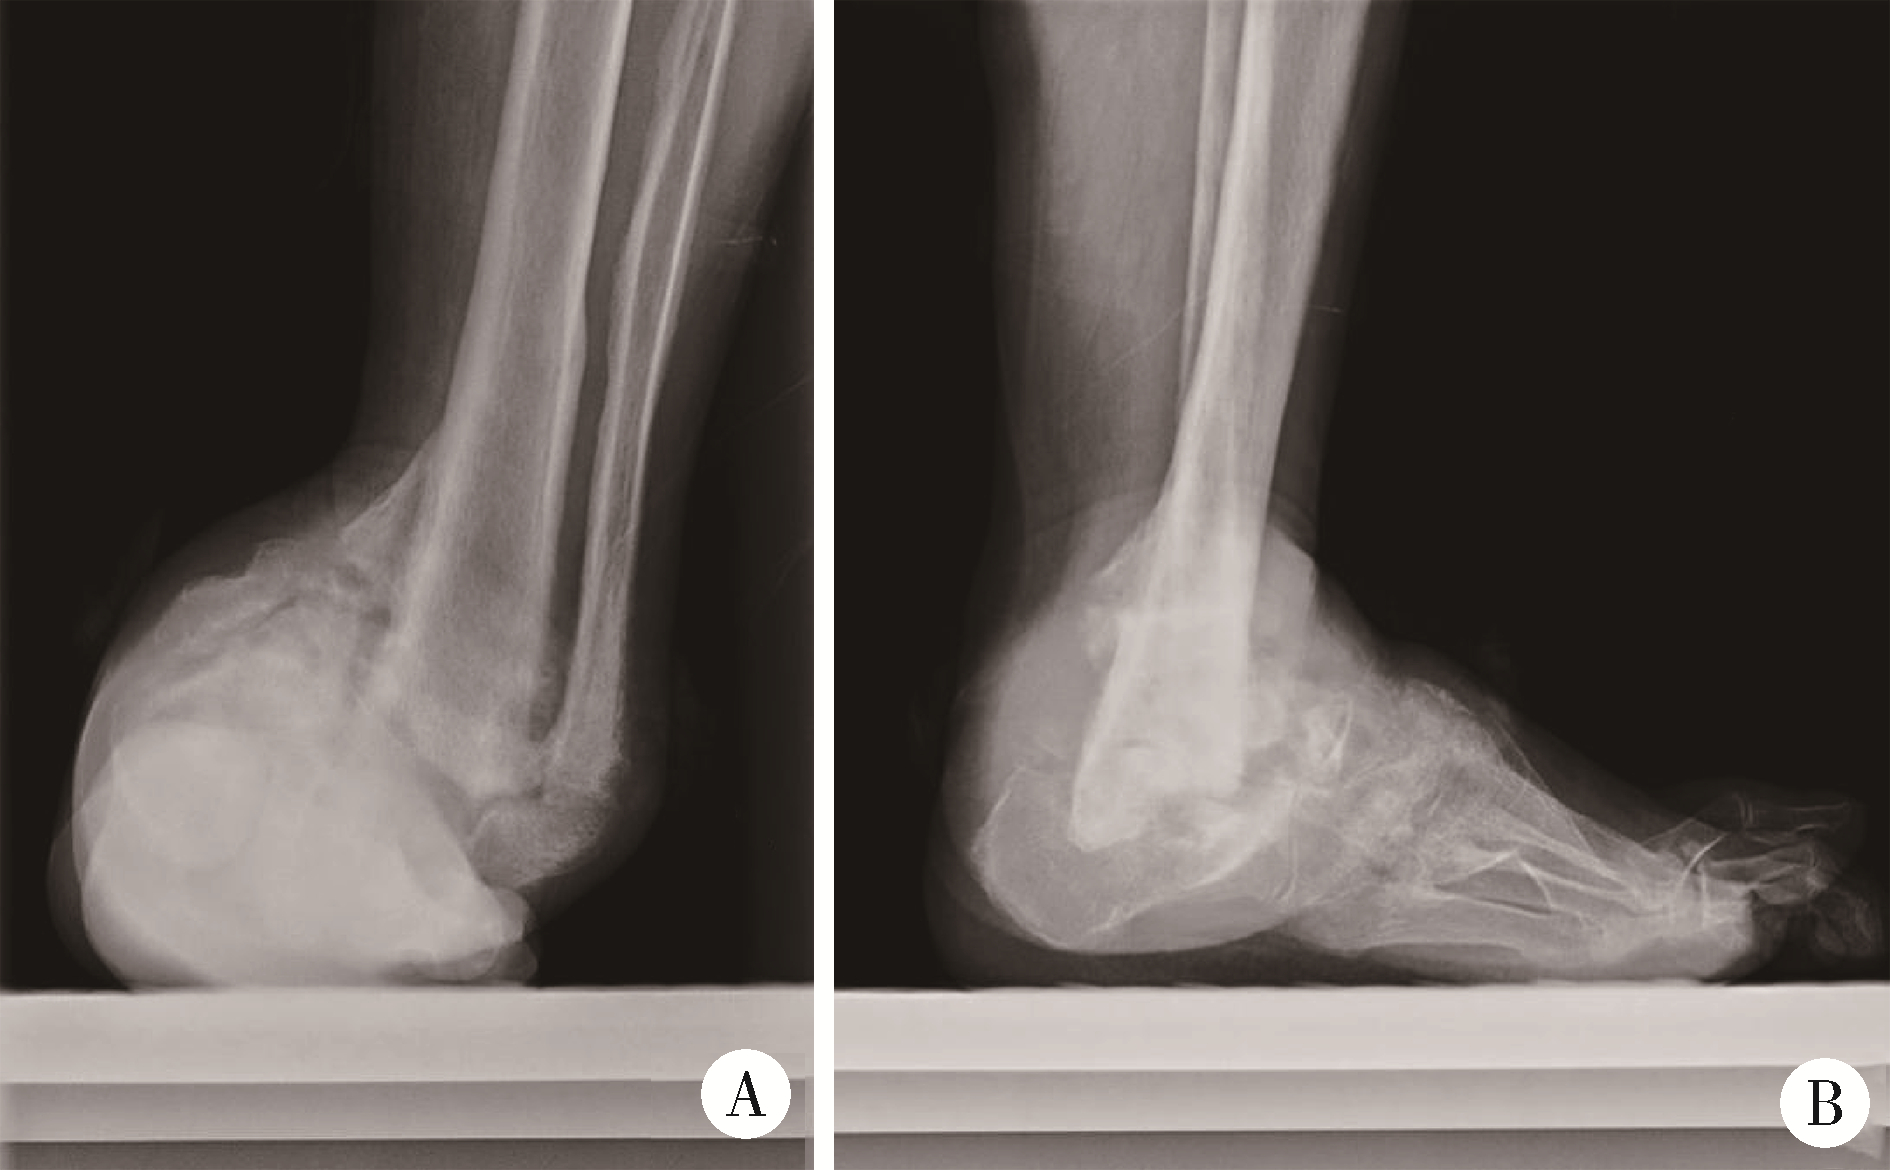

Figure 2

Weight-bearing ankle radiograph A, anteroposterior view; B, lateral view. Weight-bearing ankle radiograph shows malalignment of the left ankle joint with severe bony destruction of both the medial and lateral malleoli, as well as intra-articular loose bodies."